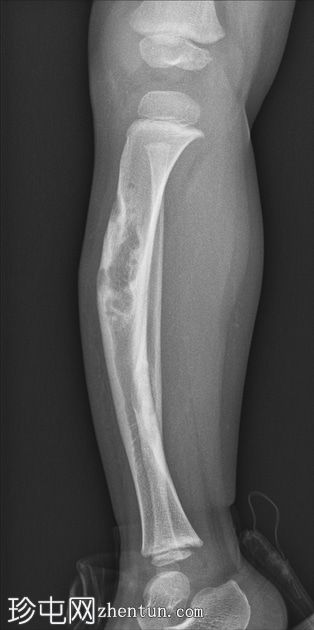

X线片

1.png

正位片

右胫骨近端骨干皮质透亮膨胀性病变,边缘硬化较薄(过渡区狭窄),导致前弓形畸形。腓骨远端骨干可见类似病变。未见骨膜反应或病理性骨折。